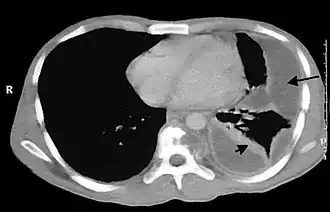

| Empiema pleural no tórax. | |

- Na cavidade pleural (empiema pleural também conhecido como piotórax);